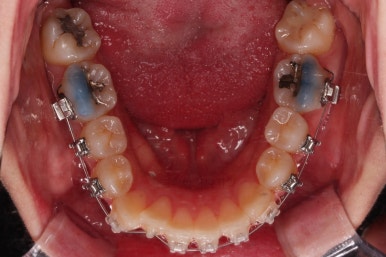

초진 시 입안의 모습입니다.

전반적으로 치열이 삐뚤고요.

위아래 중앙선이 약간 틀어져 있는데 많이 심한 편은 아니고요. 윗니가 배열된 U자 형태를 보면 아랫니보다 좁은 형태로 "악궁이 좁은" 상황이었습니다.